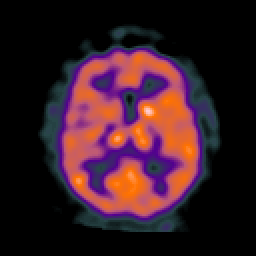

AIDS dementia: overlay -- Slice #10

[Home][Help][Clinical][Tour 1] Slice 10